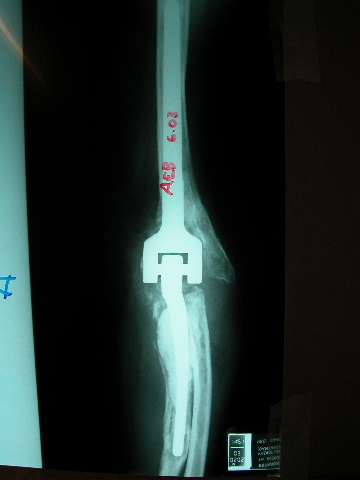

Prótesis completa de rodilla. Situación postquirúrgica.

Prótesis completa de rodilla. Situación postquirúrgica. Lateral.

Prótesis completa de rodilla.Lateral.

Prótesis completa de rodilla. Frontal.